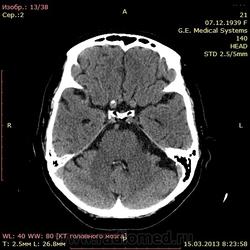

А как по мне, то тут геморрагический инсульт. Есть дислокация срединных структур слева.

Геморрагический инфаркт левой височной доли (в проекции таламуса слева) как правильно по локализации сам не знаю, скорее все таки таламус, со смещением срединных структур вправо, третий и левый боковой желудочек частично компримированы, формируется зона перифокального отека

тут либо геморрагический инсульт с перифокальным отеком, либо ишемический инсульт с геморагическим пропитыванием. Как их различить? Что скажут опытные коллеги?

Типичное медиальное кровоизлияние (в таламусе, медиальнее внутренней капсулы), уже не совсем свежее, плотность уже более низкая и зона отека приличная.

КТ признаки кровоизлияния в базальных ядрах, отделах с выраженными признаками перифирического отека. Про давность - сами пусть спросят , но скорее не свежак, до 5-6 дней.

Описывайте как геморрагический инсульт с объемным действием (смещением) на срединные структуры мозга. Померяйте плотности для оценки стадии. А различить на КТ две обговариваемые формы думаю нельзя. Разве что при пропитывании не будет такой четкой динамики изменения плотности очага. В литературе не встречал.